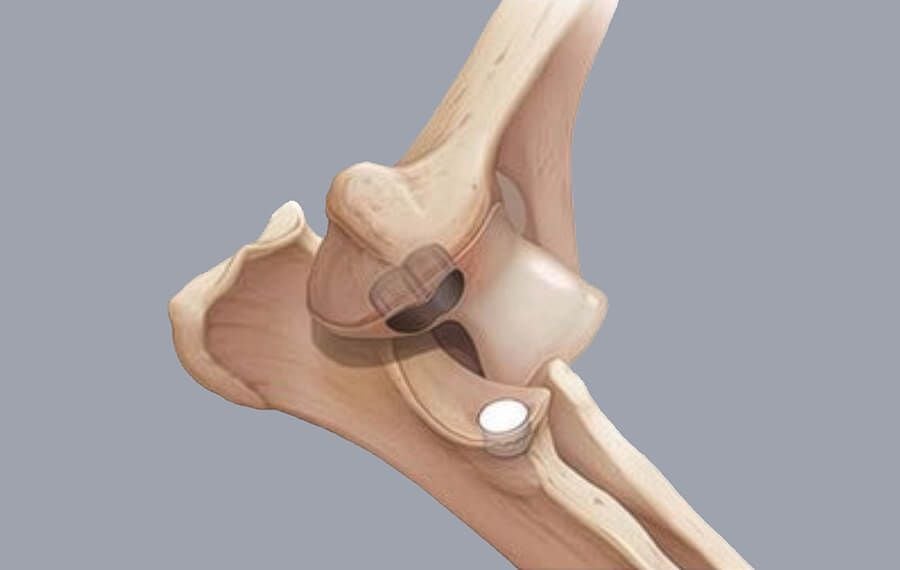

Unlike a Total Elbow Replacement for dogs, which replaces the entire joint, the CUE is a "targeted resurfacing" procedure. It focuses specifically on the medial compartment, the area where 90% of elbow pain and wear occur.

The Implants: We install a specialised metallic implant into the base of the humerus (thigh bone) and a high-strength synthetic "socket" into the ulna (shin bone).

The "Buffer" Effect: These implants meet in the middle to create a new, low-friction glide surface. This eliminates the painful grinding of raw bone against raw bone.

Preserving the Natural Joint: Because we only replace the worn-out section, the healthy "lateral" (outer) part of your dog's elbow is left completely intact. This preserves the natural stability and feel of the joint.